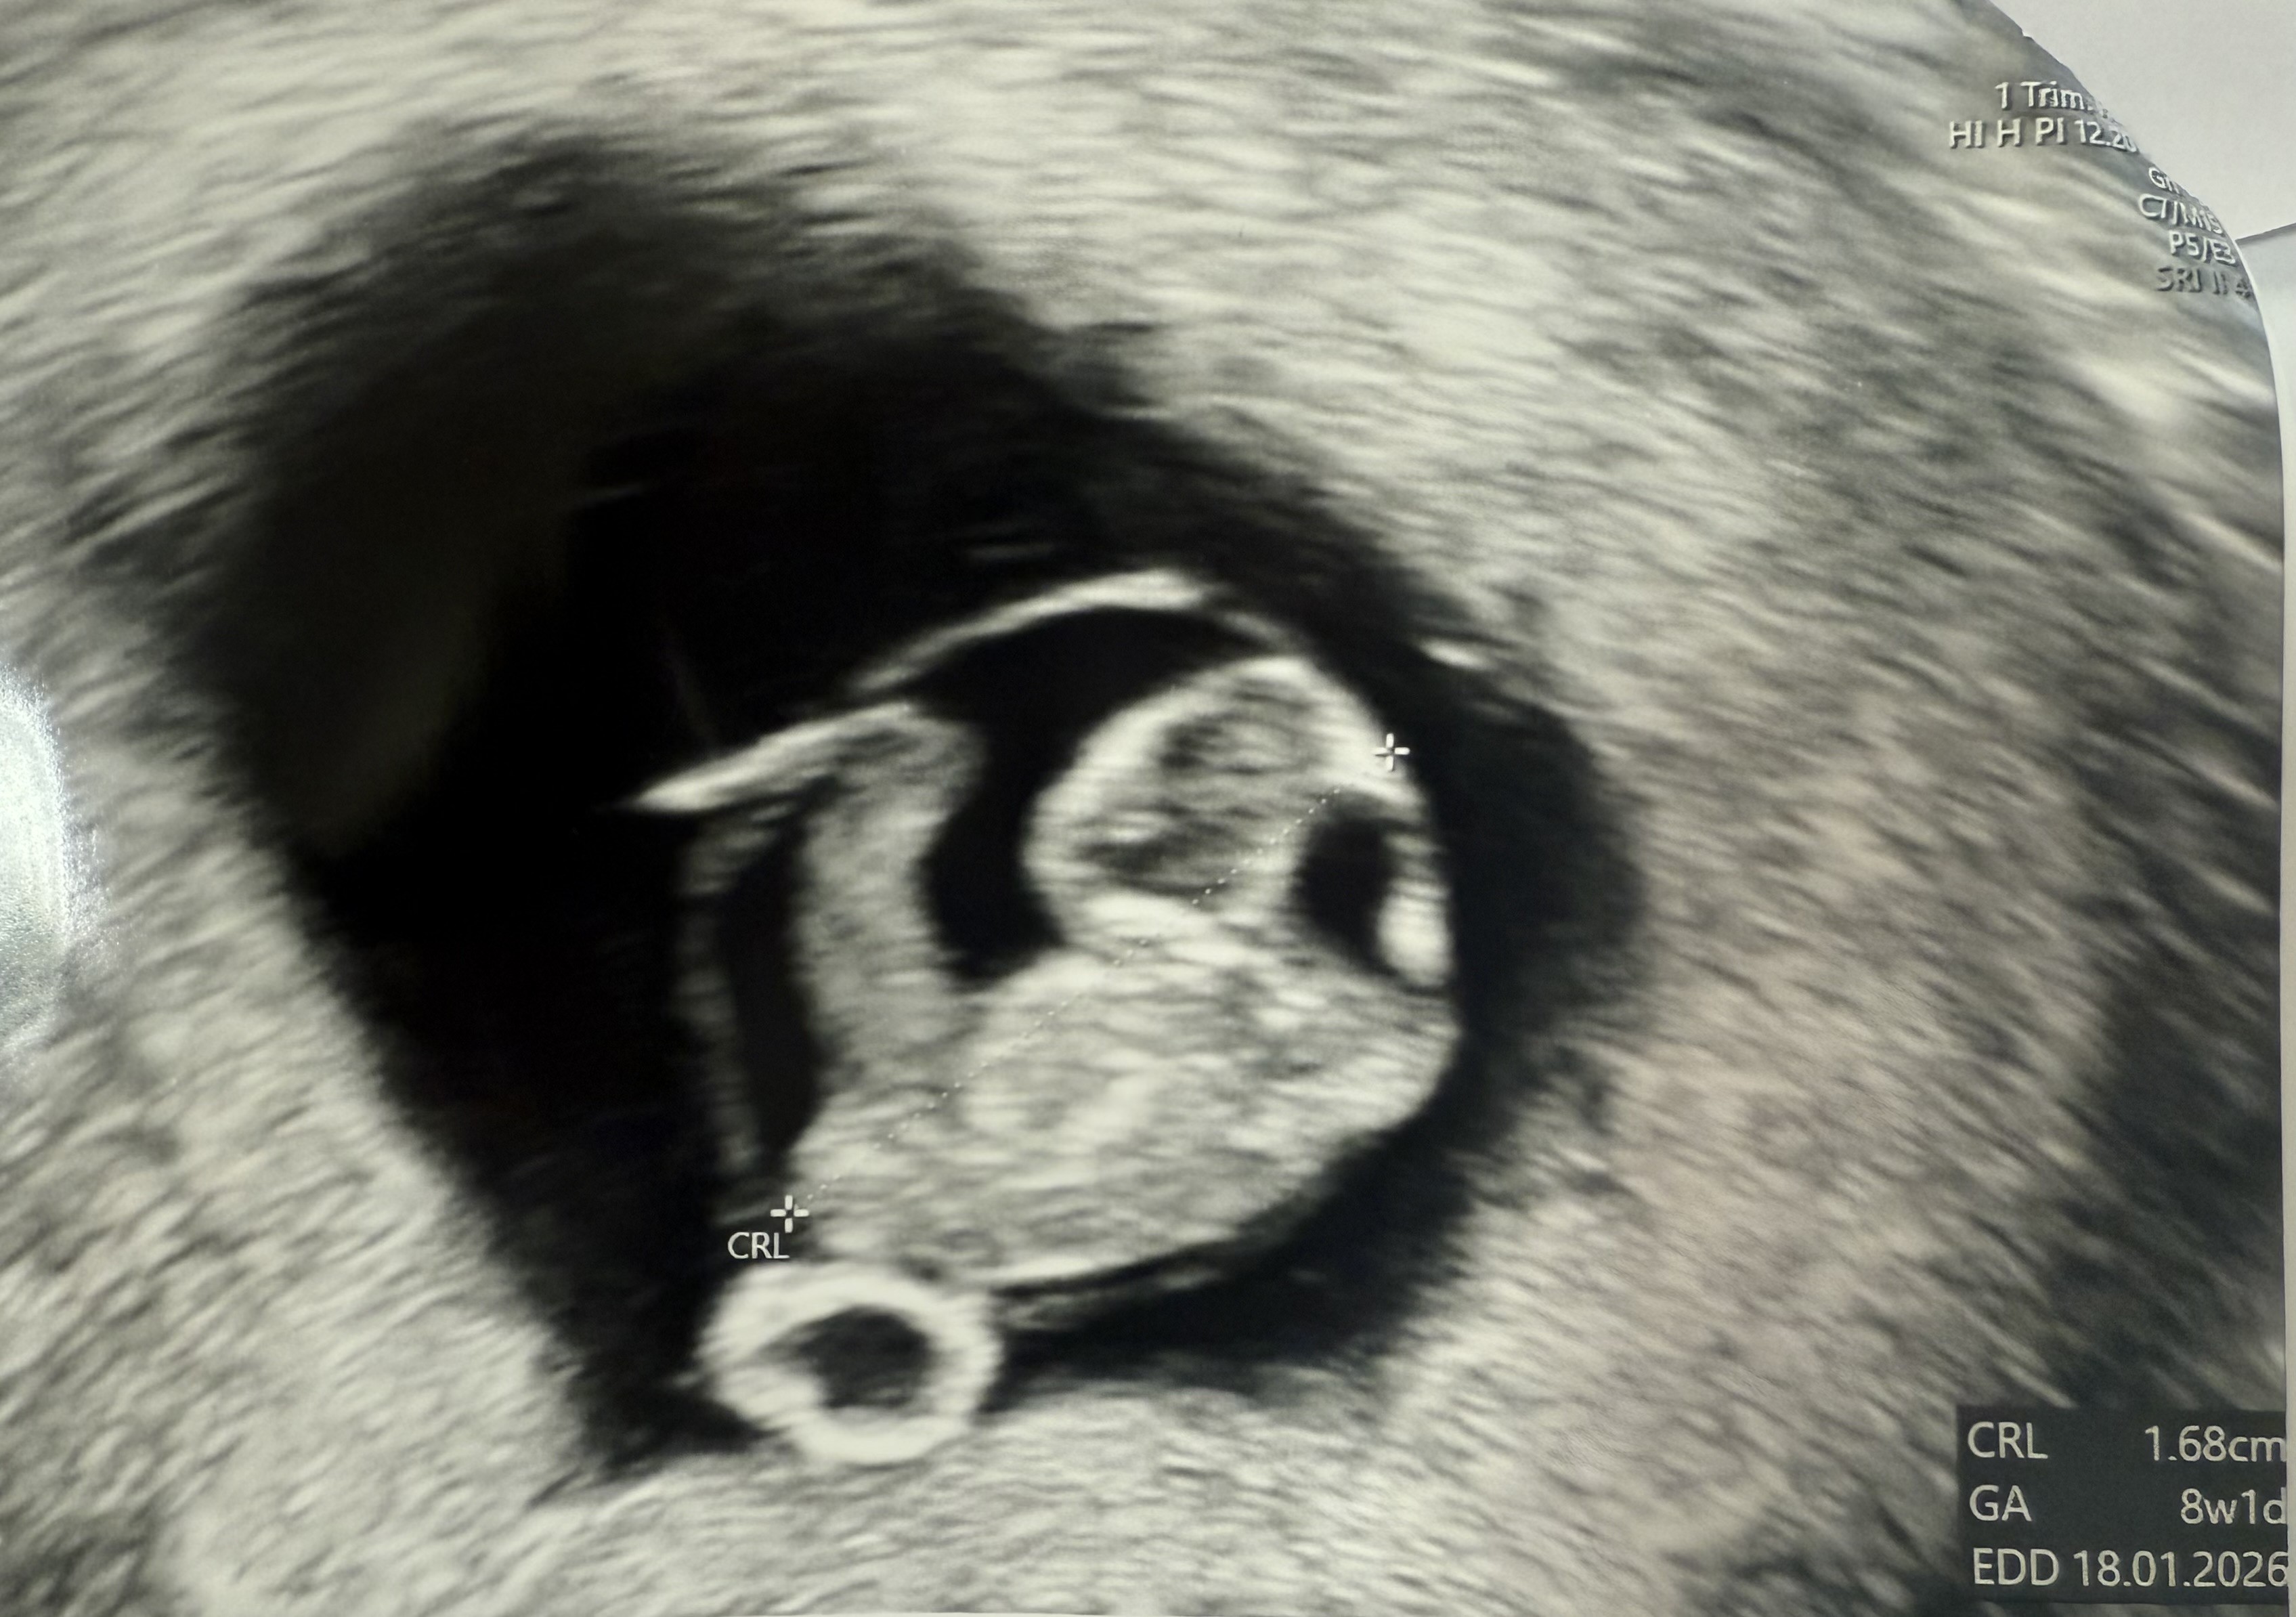

My już dziś po wizycie, też się stresowałam czy wszystko ok, na szczęście ciąża się rozwija prawidłowo, ostatnio mieliśmy 3-4 dni różnicy między OM a USG, teraz jest jeden dzień różnicy, wg OM 8+2, wg USG 8+1 i serduszko 186 uderzeń

prawie 1,7 cm dziecka